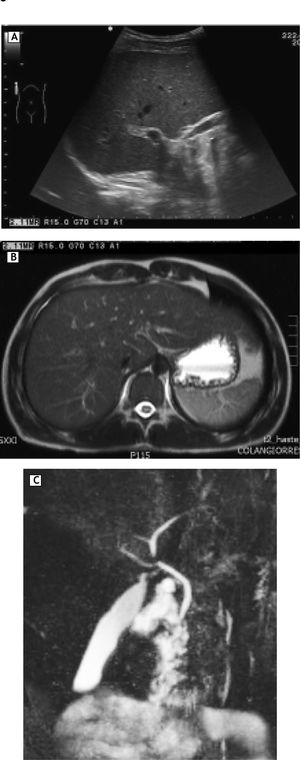

On physical examination tachycardia (120 bpm), jaundice without hepatomegaly and signs of scratching were identified. New serological tests for hepatitis A, B and C in addition to antibodies assessing autoimmune liver disease were negative; ferritin and thyroid function tests were normal (Table 2). The ultrasound showed no abnormalities in liver, gallbladder, bile ducts or intrahepatic veins (Figure 1A). Magnetic resonance cholangiography demonstrated normal appearance of extra and intrahepatic biliary system (Figure 1B and 1C). In the setting of persistent hyperbilirubinaemia, elevated ALP, ALT (more than 10 times upper normal limits) and clinical suspicious of toxic hepatitis by DES, a percutaneous liver biopsy was performed, revealing portal lymphocytic inflammatory infiltrate with scattered eosinophils, inflammatory damage to interlobular bile duct (ILBD) epithelium, moderate ductopenia (absence of ILBD in 3 out of 8 portal tracts), marked perivenular intracytoplasmic and canalicular cholestasis in the lobule, with mild hepatocellular swelling and eventual multinucleation (Figure 2).